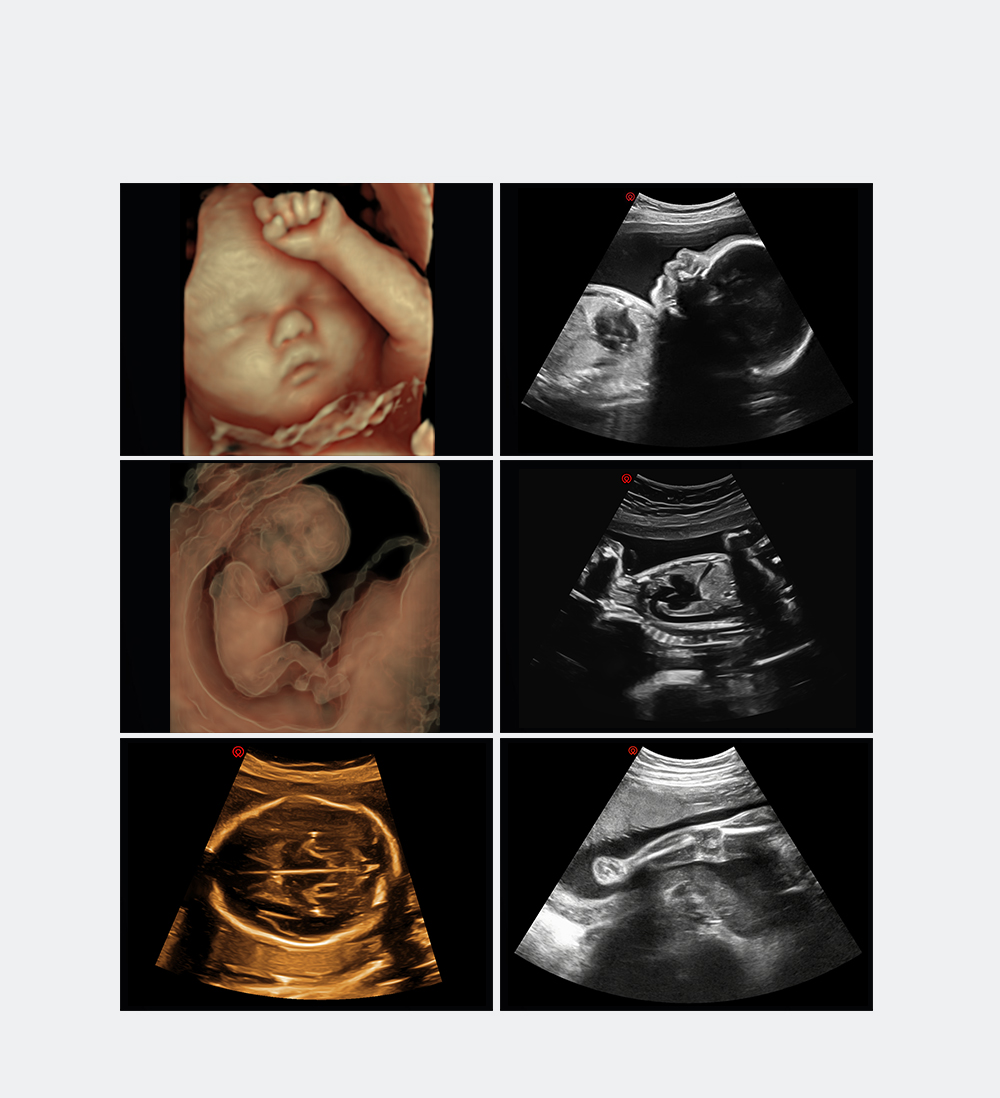

Système Intelligent d'échographie de Dépistage Obstétrical

Plateforme CS de pointe dotée d'une technologie d'imagerie super-résolution unique dans l'industrie

Conceptions ergonomiques et flux de travail d'IA efficace, offrant une expérience utilisateur extraordinaire